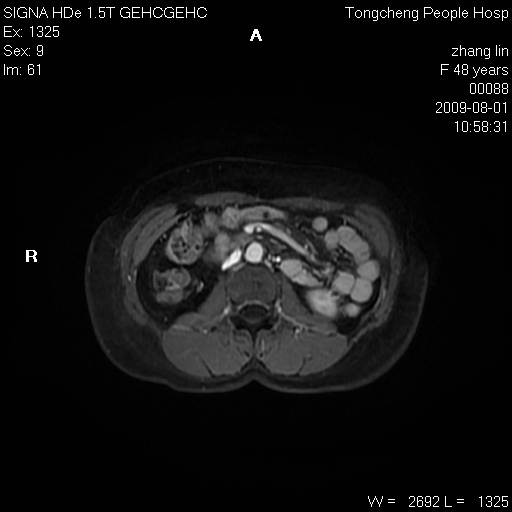

女,48岁。健康体检,彩超发现右肾占位性病变。平素健康。

临床诊断:右肾占位性病变,性质待定(囊肿?肿瘤?)。

上中腹部mr平扫+增强扫描,图像如下:

右肾上极见一类圆形病灶,t1wi呈等信号t2wi呈等高混杂信号,三期增强无强化,边界清---考虑囊肿出血。

同反相位均表现为等信号,病变无强化,考虑含蛋白的囊肿可能,弥散加权相或许有些帮助,